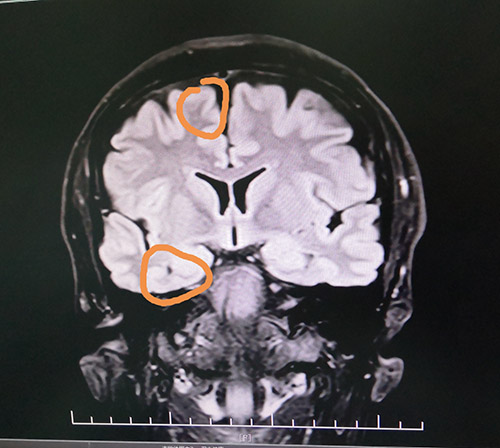

头颅海马MRS检查显示:右侧海马Cho/NAA+Cr=0.5;左侧海马Cho/NAA+Cr=0.56。PET-CT检查显示,右侧颞区FDG代谢减低。视频脑电图(VEEG)显示,在清醒状态下,额区和颞区显著,各导联较多异常波阵发出现。在睡眠状态下,颞区有少许高-极高波幅尖波、尖慢波左右不同步单发、偶波及额极、额区(右侧显著、多以睡眠期出现)。

▲患者癫痫病灶区

蓝十字脑科功能神经外科主任杨忠旭博士认真查看了刘先生各项检查报告并听取相关病情汇报,认为患者脑组织结构发生病变,引起癫痫发作,经系统药物治疗无任何改善,应用现代神经影像学技术和电生理监测技术,能明确引起癫痫发作的的“责任病变”。

在征得患者家属同意后,10月28日上午,杨忠旭博士在助手杜立功及医护团队协助下为刘先生进行了“癫痫病灶切除术”手术。由于患者患有高血压、脑萎缩,脑血管异常脆弱,且局部脑组织结构异常,多处异常放电部位,为手术带来挑战,手术中需要格外小心。在全程脑电监测下,杨博士处之泰然,游刃有余,在助手密切配合下,为患者切除了颞叶、海马和额叶病灶。癫痫病灶切除后,再次监测脑区,无异常放电,手术成功。紧接着彻底止血,严密缝合硬脑膜,复位骨板……紧张的手术终于结束。